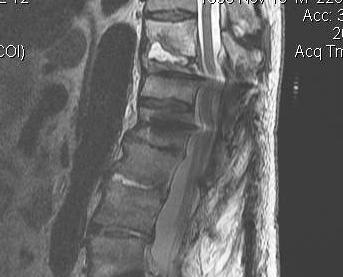

MRI with Gadolinium

Investigation of choice

- well vascularized inflammatory tissue enhances on T1

Osteomyelitis changes include

- confluent hypointensity of involved bodies on T1

- hyperintensity of involved bone and disc on T2

- loss of distinction of involved bone & disc

- abnormal disc appearance

Epidural abscess